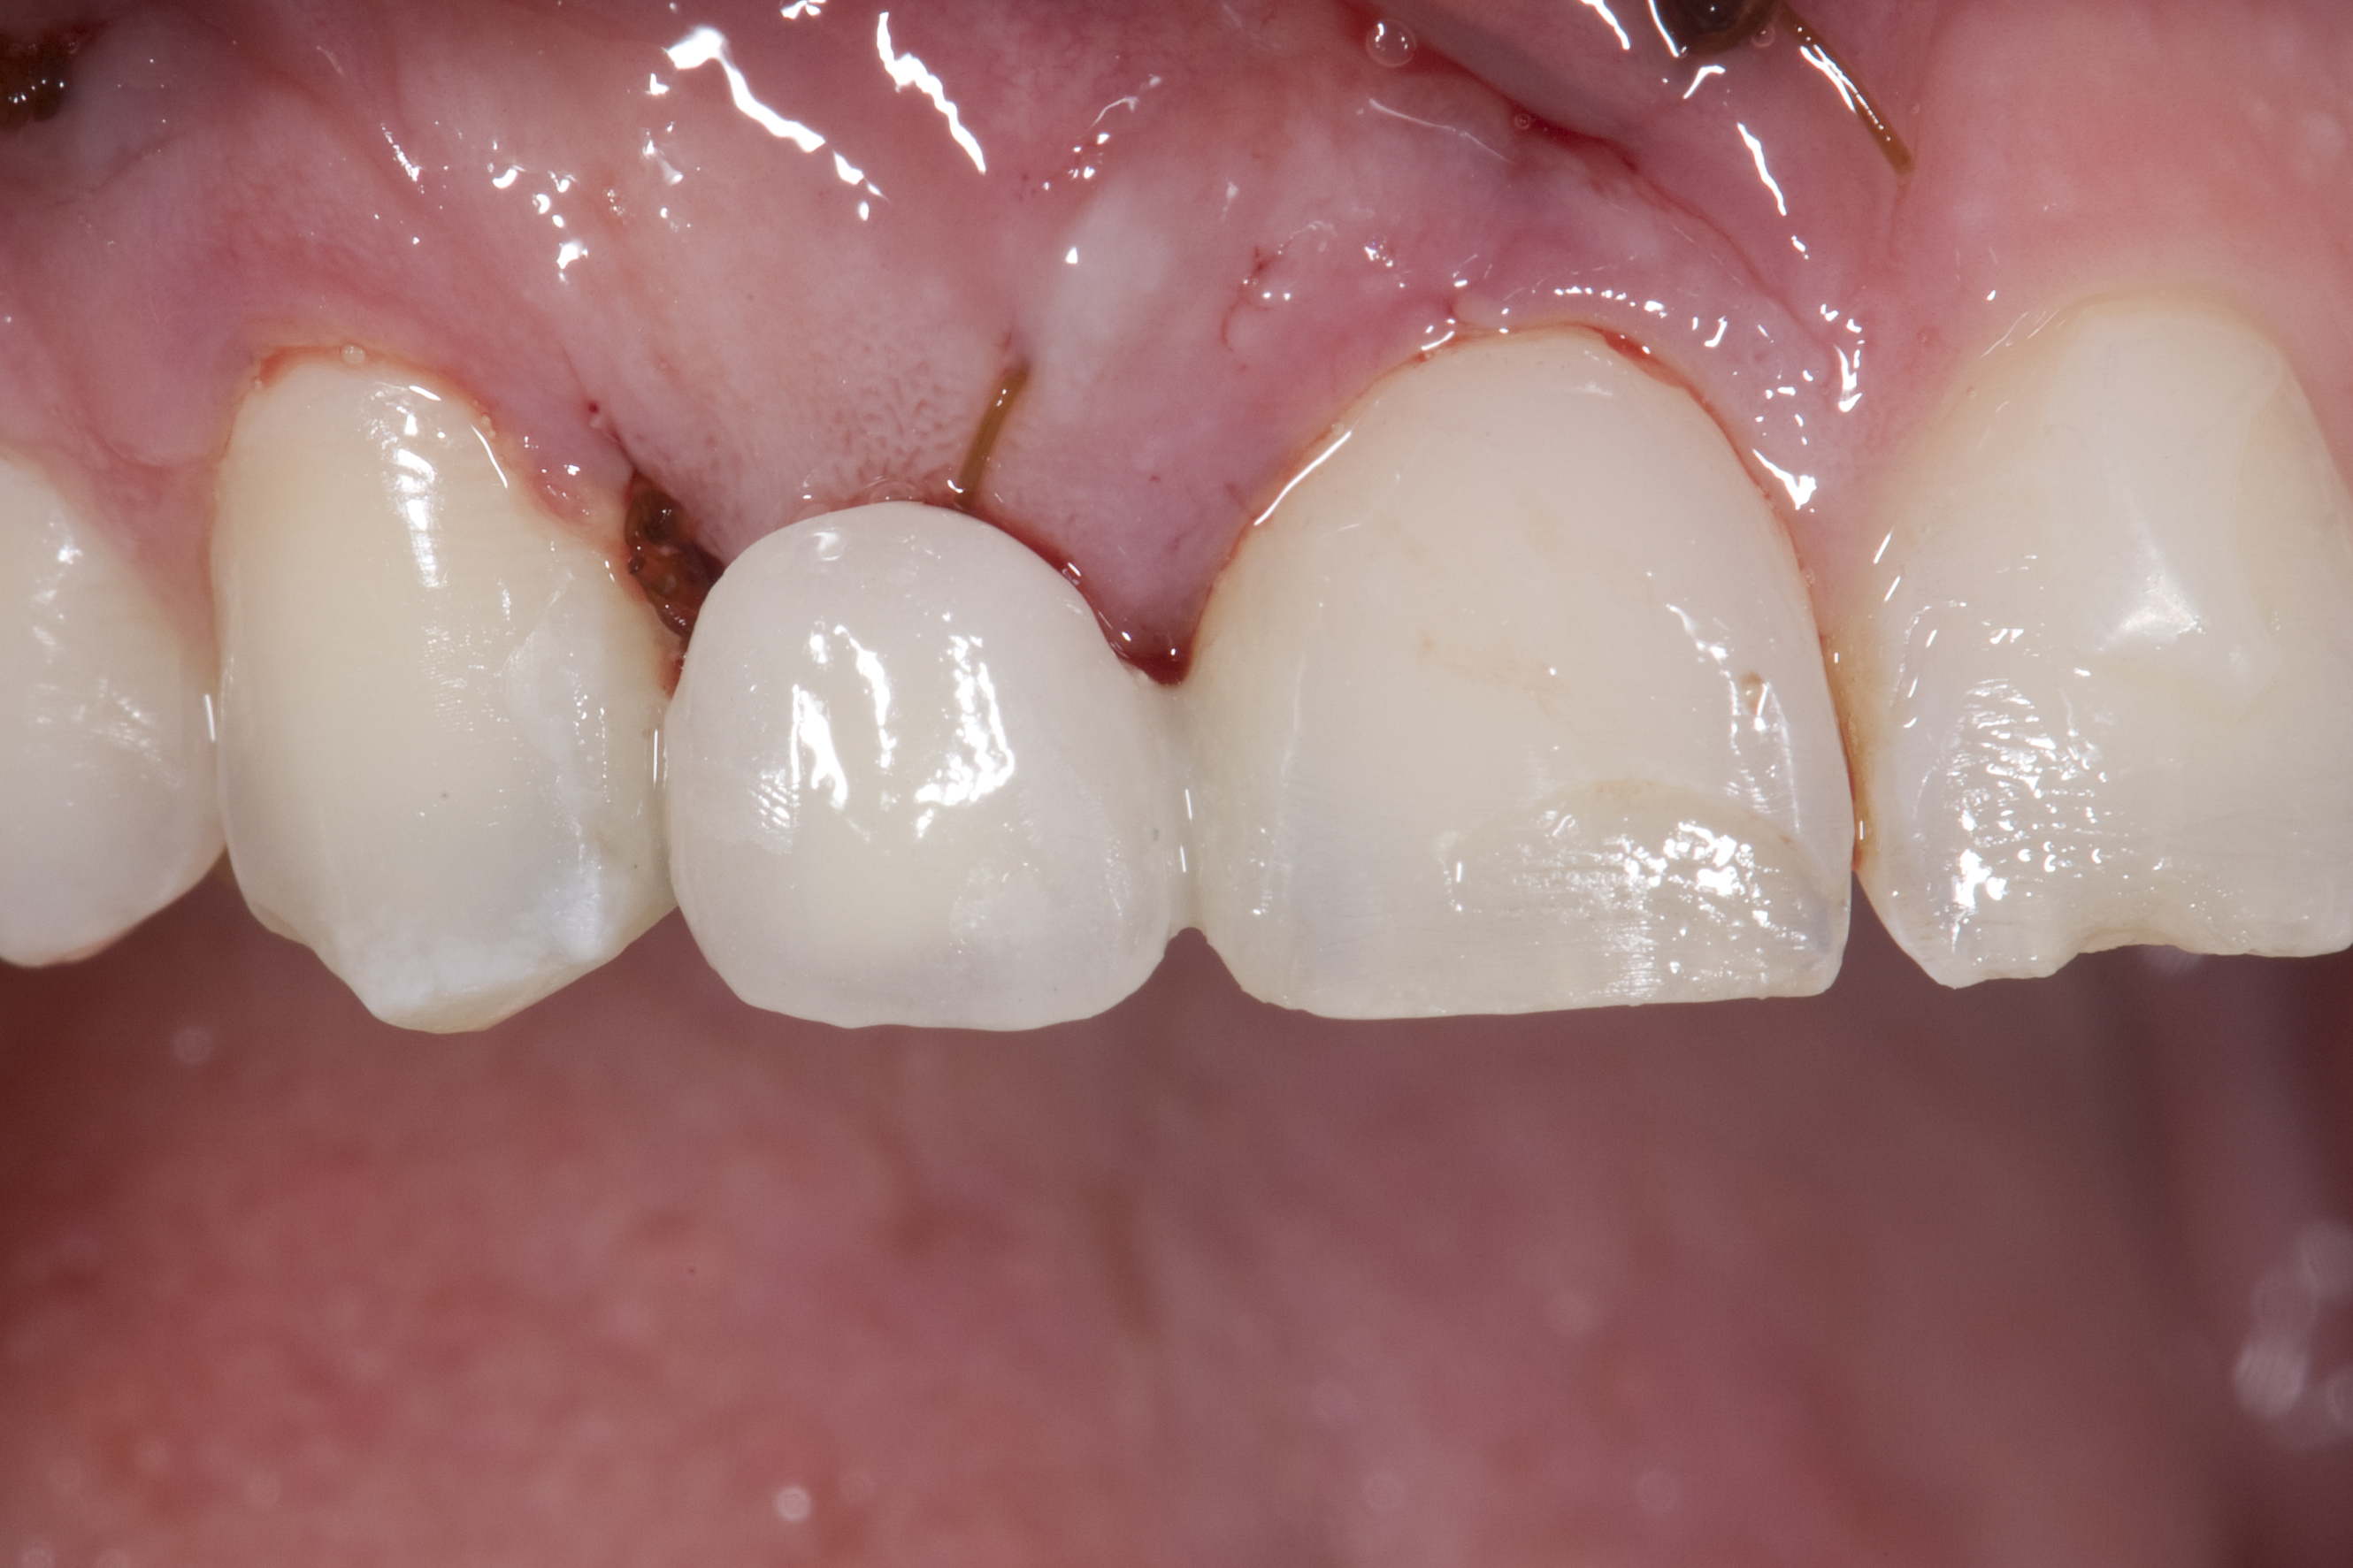

(13.) Deficient ridges in the areas of the missing lateral incisors.

Figure 13

Some patients do not want an implant due to the need for surgical intervention, and others may not have enough space for implant placement. A 15-year-old patient presented to the office after completion of orthodontic treatment to idealize the spacing of her teeth and improve her occlusal relationship (Figure 12 through Figure 14). Because both of her maxillary lateral incisors were missing, the patient was wearing a retainer with lateral incisor pontics. She had a busy school schedule, but expressed her desire for a fixed restorative option. All of her options were discussed, and the patient was informed that if she wanted an implant, she would have to wait for at least 3 to 4 years for completion of growth. The patient was not sure if or when she wanted to have an implant placed in the future, especially considering her busy schedule and desire to attend college after high school. Considering her age and the need to be conservative, a single-wing zirconia Maryland Bridge was chosen as the ideal prosthetic replacement option. Because bonding a non-etchable and smooth surface such as zirconia requires chemical adhesion, it was decided to use a modified technique to make the bridge more retentive. One of the ways to improve adhesion of a zirconia bridge is to use an etchable feldspathic ceramic layer on the internal surface of the zirconia retainer.56-58 Unfortunately, it can be difficult to determine the thickness of the ceramic and ensure accurate seating of the restoration.